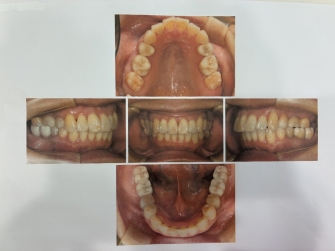

当歯科ではレントゲンをお取りしたり、現状を記録するためにお口の写真を撮らせてもらっています。左のの大きなレントゲンは3割負担の方で1200円、右のお口の写真は150円です。実際にお口の状態を目で見てもらうと一目瞭然。経過を比べると歯肉がどれくらい健康になってきているか、きれいになっているがわかります。そしてそれを記録することに意味があります。

処置も症状が出る前のほうが簡単に済むことが多いです。当歯科では2年に一度はこのレントゲンを撮らせてもらって経過を見ることにしています。症状があればその都度大きいレントゲンではなく、部分的なレントゲンを撮って確認することもあります。小さいレントゲンは150円くらいです。